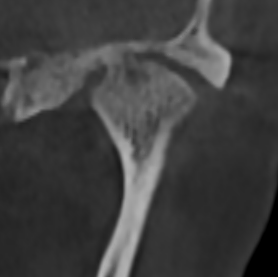

Перед началом лечения я провожу часовую первичную консультацию. Для этой встречи вам необходимо сделать «МРТ ВНЧС» и «КЛКТ двух челюстей с захватом ВНЧС в привычном прикусе».

Во время консультации мы смотрим и анализируем ваши исследования. Я подробно объясняю строение ВНЧС, показываю все причинные факторы вашей проблемы, отвечаю на все вопросы «Почему?»